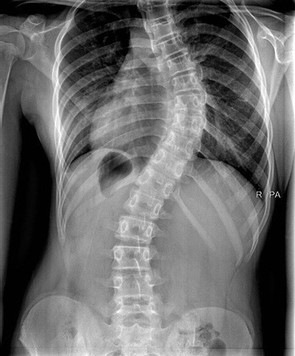

- De corriger ou prévenir l’aggravation d’une déviation de la colonne vertébrale

Les corsets correcteurs et de maintien:

- Chêneau, CTM, Milwaukee, Boston, ...